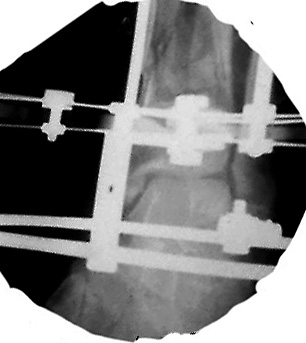

Tibia Fx ForumCase 1

I would appreciate treatment suggestions.My patient is a 30 year old with a very comminuted tibia fracture 6 weeks ago.It was grade 3B open. Initial treatment included irrigation, debridementClick images to enlarge.

and a hybrid external fixator including femur, tibia and foot. Screwswere placed in the plateau and plafond and a free flap plus STSG. Theskin is ok but atrophic. The femoral pins were removed and knee motionstarted at 6 weeks. There is no sign of callus. There is one pin inthe one large fragment of the diaphysis. All the pieces are lined upreasonably well. The XF pins are ok. Suggestions? Thank you.